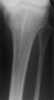

Osteopathia striata